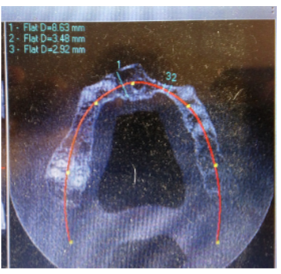

5) Maxillary CT scan confirms that there is 3.5mm (maximally) of ridge present UL anterior region